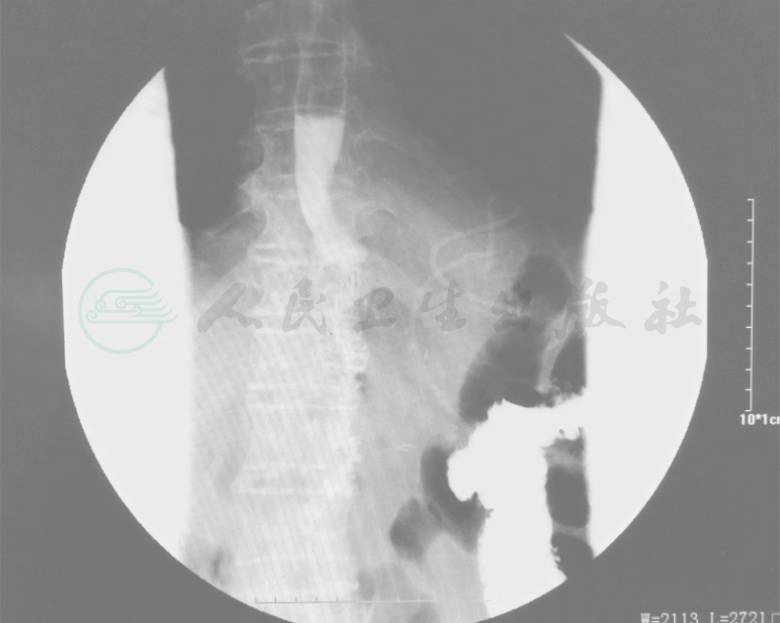

胃镜示:食管、贲门及胃底隆起性病变;病理活检示:低分化腺癌。全腹部CT示:食管-胃底胃壁增厚,增强扫描明显不均匀强化,符合食管-胃底癌改变(图1、图2)。

图1 食管胃结合部占位